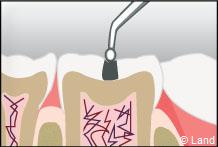

Les traitements possibles pour les stades de la carie où seuls l’émail et la dentine sont touchés peuvent se faire avec de l’amalgame qui est un matériau indiqué dans la restauration des petites et moyennes cavités.

L’amalgame est utilisé sous forme de capsules prédosées et avant son utilisation est préparé par un vibreur qui mélange les composants de façon homogène. Il se présente sous la forme d’une pâte, plastique qui durcit dans la cavité nettoyée de la lésion carieuse et devient pratiquement aussi résistant que les tissus dentaires.